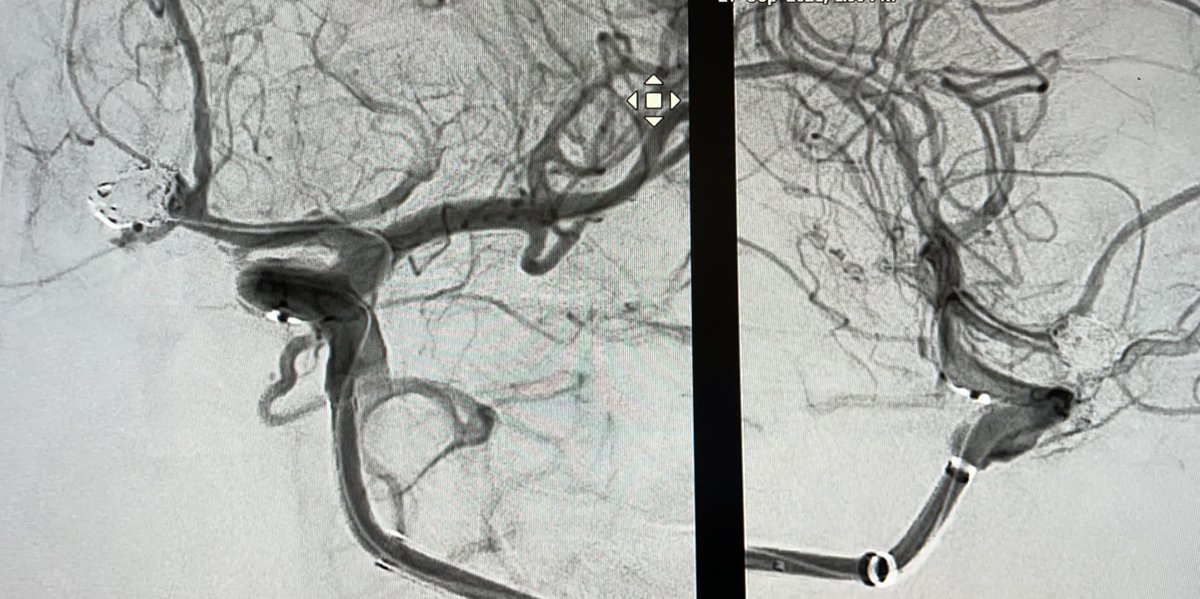

El Dr. Carlos Pérez@Justcharly9, nos resume en menos de 15 minutos los dos principales ensayos clínicos que comparan tratamiento Endovascular VS Quirúrgico (ISAT, IBRAT) de aneurismas rotos.